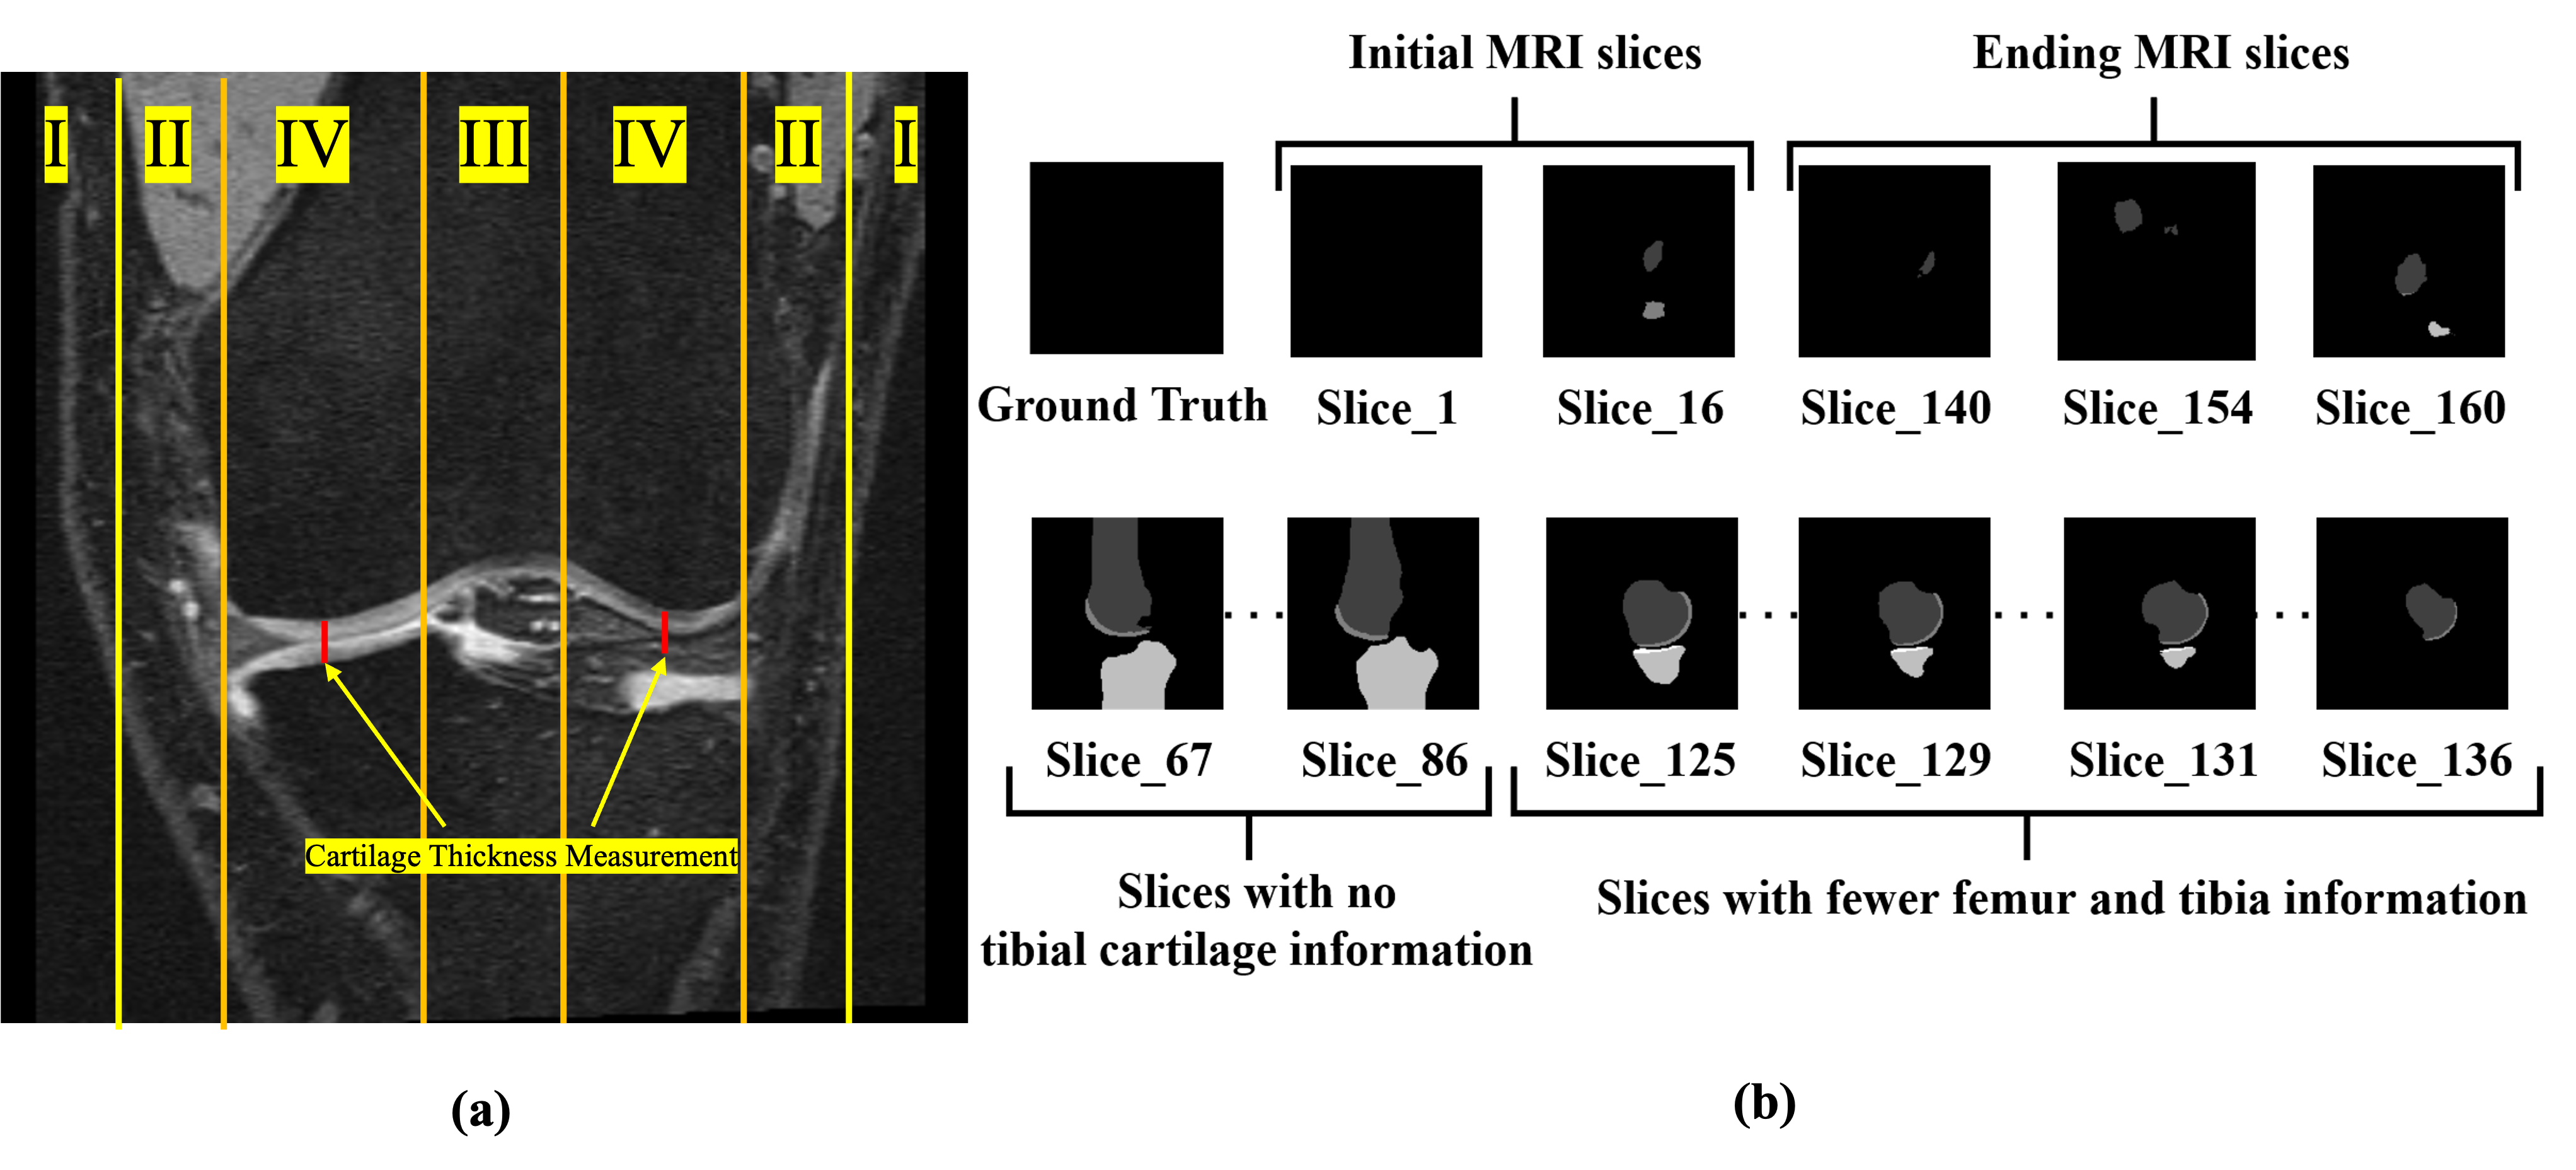

3.5 ROI computation and strategy to reduce false positives

To improve diagnosis efficacy and lessen false positives for prediction in KOA, it is required to concentrate more on the ROI slices that contain femur, tibia, and tibiofemoral cartilage. To fulfill these requirements, the criterion of Deng et al.[3] was found to be appropriate. According to the criterion, the performance evaluation must be carried out on only those slices that meet the minimum pixel count rule. The threshold in this rule is chosen in such a way that it can confine those ROI slices that contain only the weight-bearing region in the knee. The weight-bearing region is identified as 20% of the total maximum medial-lateral cartilage width for each condyle [31], [32] during walking, as illustrated in Figure 5 (A), where the cartilage thickness measurement has significant influence in KOA grading [31]. This criterion is observed to filter out (1) the slices with no tissue information (initial and ending MRI slices) that often produce false positive results, (2) the slices with fewer occupancy of femoral and tibial bone pixels and (3) the slices with anterior and posterior cruciate ligaments that have no tibial cartilage information when the image size is adjusted to 150*150 as represented in Figure 5 (B). It is important to note that, the segmentation from the “MtRA-Unet” Model is performed for all the knee MRI slices per volume. However, the evaluation is measured only for those slices that are critical in the diagnosis of KOA.

Refer to caption

Figure 5: (a) Coronal and (b) Sagittal view of MR slices with the depiction of (I) initial and ending slices (i.e. noise-only slices with no tissue information), (II) slices with fewer occupancy of femoral and tibial bone, and (III) slices with anterior and posterior cruciate ligaments (that contain no tibia cartilage information), and (IV) medial-lateral regions (selected for segmentation analysis) for subject ID: 9471287